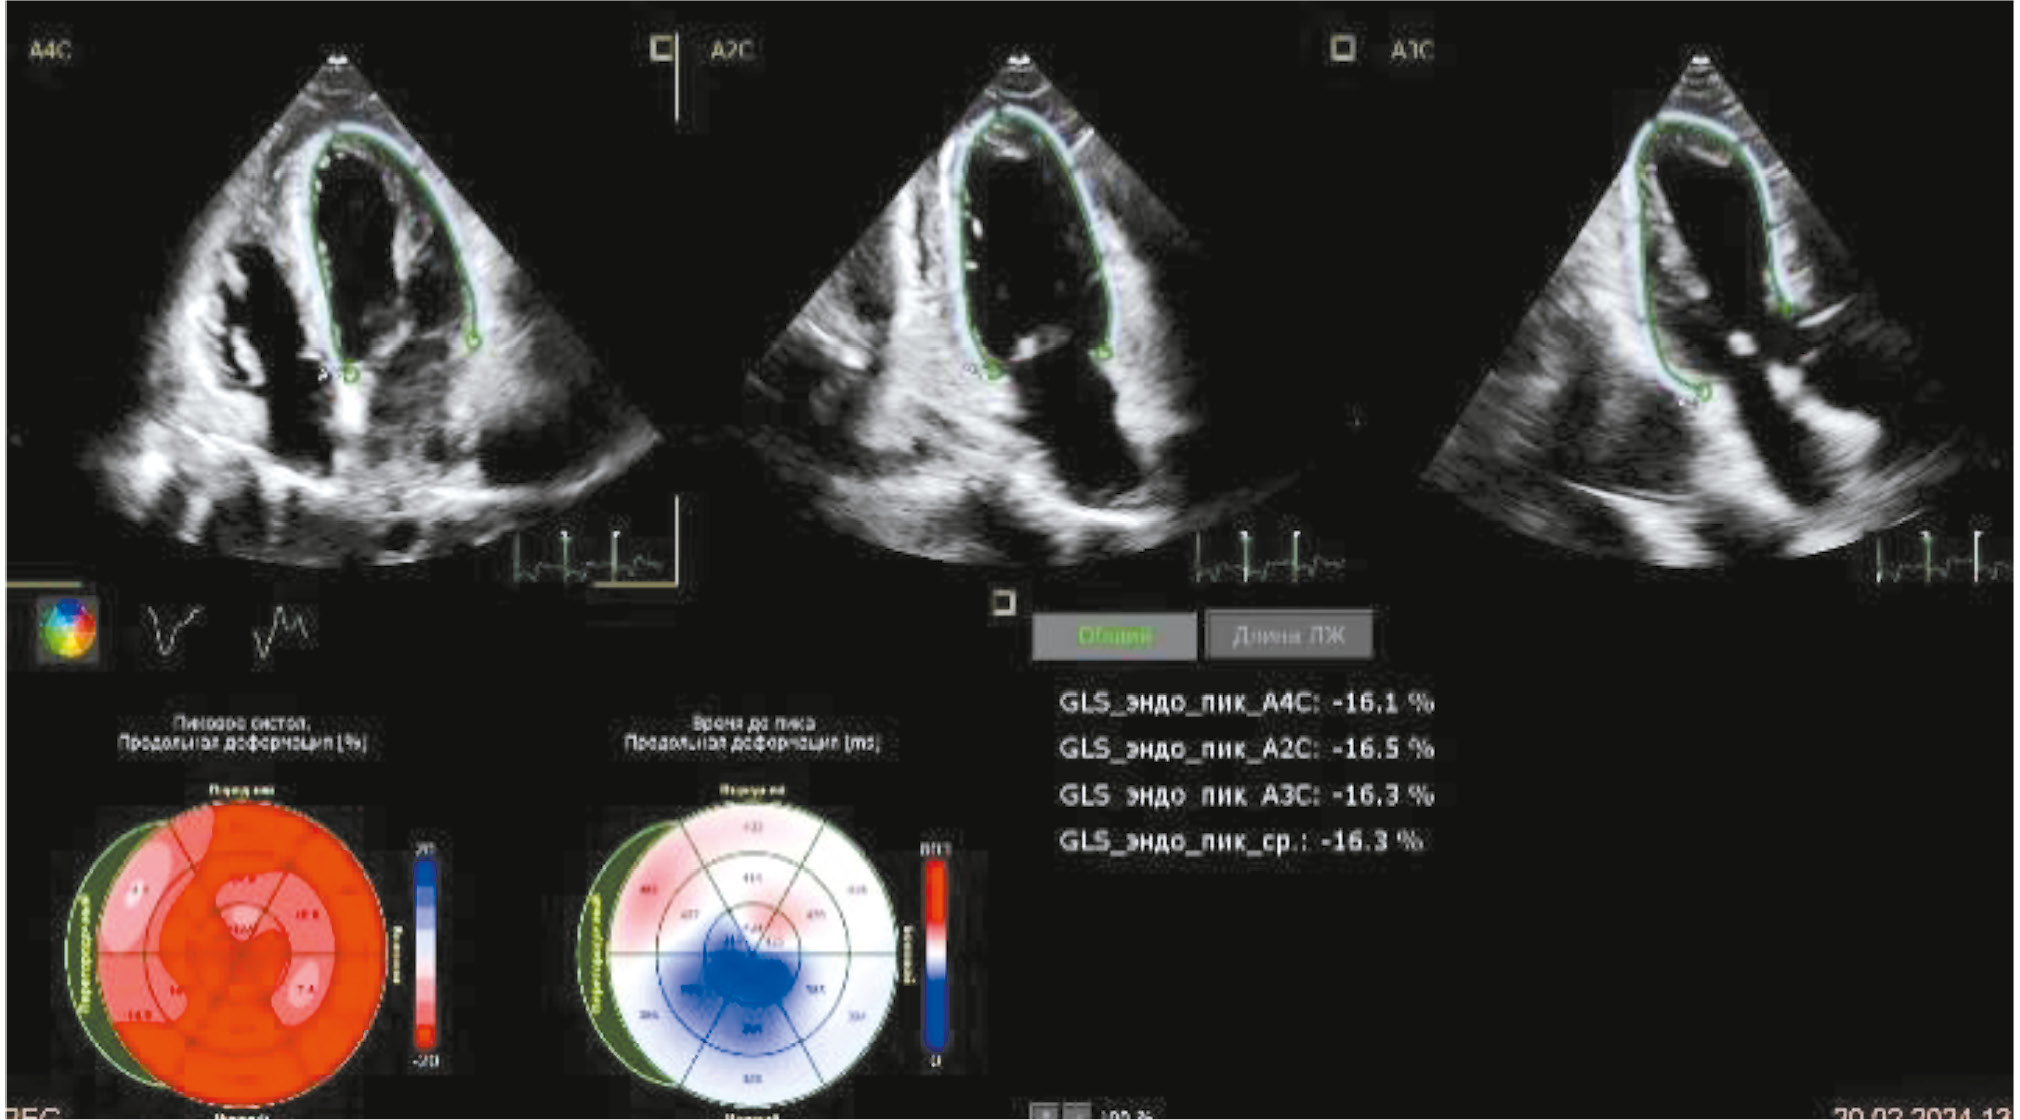

Рис. 7. Эхокардиография на десятые сутки госпитализации: показатели глобальной деформации левого желудочка.

Fig. 7. Echocardiography on the 10th day of hospitalization: indicators of global left ventricular strain.

В отделении кардиологии пациентка получала эналаприл 5 мг в сутки, бисопролол 2,5 мг в сутки, амлодипин 2,5 мг в сутки, спиронолактон 25 мг в сутки, аспирин+клопидогрел, аторвастатин 80 мг в сутки, омепразол 20 мг в сутки, также были выполнены дообследования. По данным ЭхоКГ в динамике от 12.02: ФВ ЛЖ 46%, толщина МЖП 14,5 мм, толщина ЗС ЛЖ 14,5 мм, ЛЖ асимметрично гипертрофирован, на фоне пробы Вальсальвы признаки динамической ОВТЛЖ с умеренным ростом градиентов (Vmax — 3,5 м/с, dPmax — 48 мм рт. ст.), акинезия всех верхушечных сегментов и срединного сегмента МЖП. При этом при выполнении третьего ЭхоКГ-исследования на десятые сутки госпитализации (рис. 5–7) зон нарушения локальной сократимости выявлено не было, ФВ ЛЖ выросла до 61%, глобальная деформация ЛЖ снижена до -16%, МЖП — 15 мм, ЗС ЛЖ — 13–15 мм, передне-систолического движения створки митрального клапана не отмечалось, так же как и признаков ОВТЛЖ.